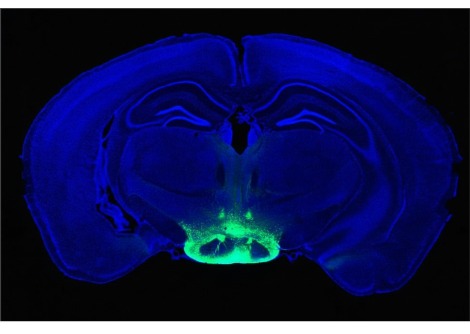

قام فريق من الباحثين بإدارة توشيفومي يوكوتا ، دكتوراه ، من قسم الوراثة الطبية بجامعة ألبرتا في إدمونتون بتجارب تجريبية باستخدام الأنابيب العضلية للمريض (تنمو ألياف هيكلية ذات مظهر أنبوبي). تم اختبار العقار الاصطناعي الجديد أيضًا على الفئران . وجدت علامات على إنتاج الديستروفين ، وبناء العضلات ، وتحسين وظائف القلب . أظهرت النتائج أن استهداف خمسة اكسونات يمكن أن يساعد في تخطي exons 45 إلى 55 . ذكر Yokota أن كل جزيء من جزيئات اكسون التي تم إنشاؤها سابقًا قد عالج بنجاح ما لا يزيد عن 10٪ من المرضى المصابين بضمور دوشين العضلي . يمكن أن يُعزى هذا إلى وجود طفرات متباينة في اكسونات في مواقع متنوعة داخل الجين . وبالتالي ، حاول فريق البحث تخطي أكثر من 11 إكسونًا معًا بهدف توفير علاج لما يقرب من 45٪ من المرضى .

يلقي البحث الضوء على عملية تعزيز تخطي exon 51 باستخدام DG9 ، وهو ببتيد . أدى العلاج إلى تحسين استعادة بروتين ديستروفين ووظيفة العضلات في نموذج للمرض عند فأر. يبدو هذا الإجراء الإستراتيجي الجديد لتخطي exon مناسبًا لأنه يستخدم أوليغومرات معينة (جزيء خاص يتكون من عدد قليل من وحدات التكرار المتشابهة أو المتطابقة) التي تساعد الخلايا على تصنيع بروتين ديستروفين أصغر ولكنه يقوم بشكل متوسط بالوظائف في المرضى المصابين .